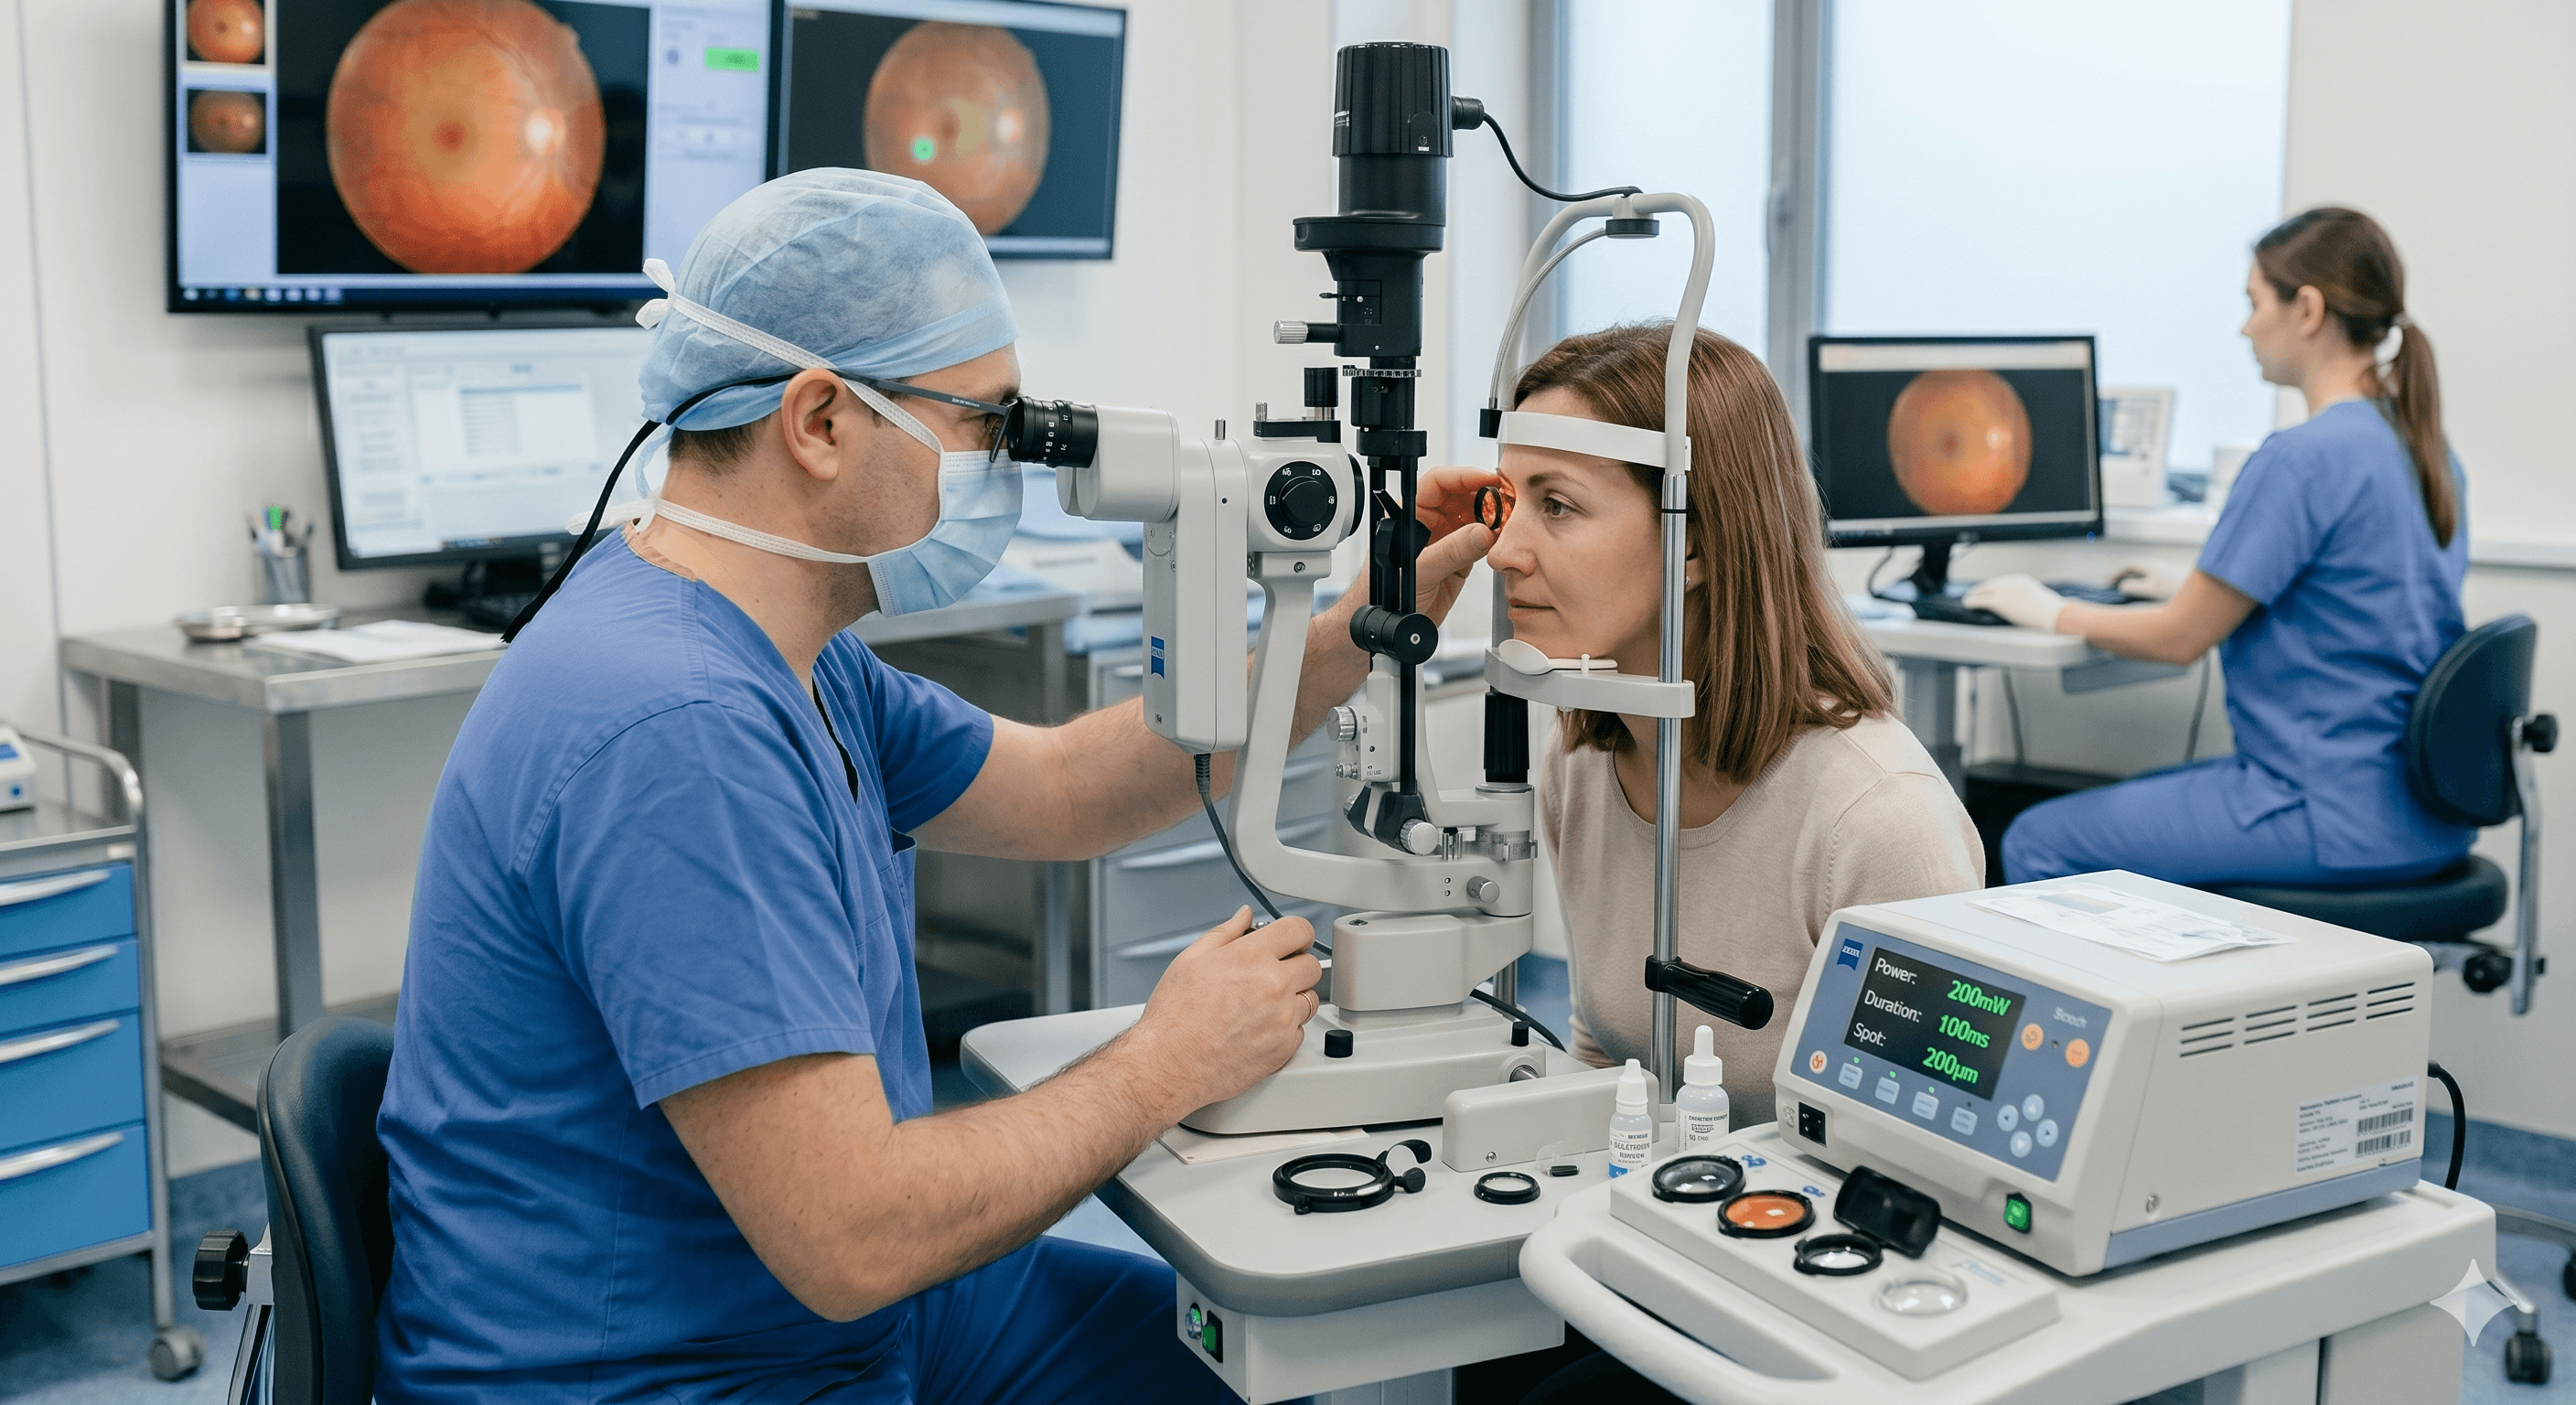

El Dr. Erick Eduardo Mena Linares es un experto en alta especialidad de microcirugía de córnea y cirugía refractiva. Con más de 8 años de experiencia, lidera una práctica enfocada en la precisión técnica y la excelencia clínica.

Inversión en tu salud visual

Obtén un diagnóstico preciso y un tratamiento personalizado con tecnología de vanguardia para el cuidado de tus ojos.

Laser para retina

Intervención oftalmológica especializada para el tratamiento y corrección visual mediante tecnología de última generación.

Capsulotomía láser

Intervención oftalmológica especializada para el tratamiento y corrección visual mediante tecnología de última generación.

Iridotomía láser

Intervención oftalmológica especializada para el tratamiento y corrección visual mediante tecnología de última generación.